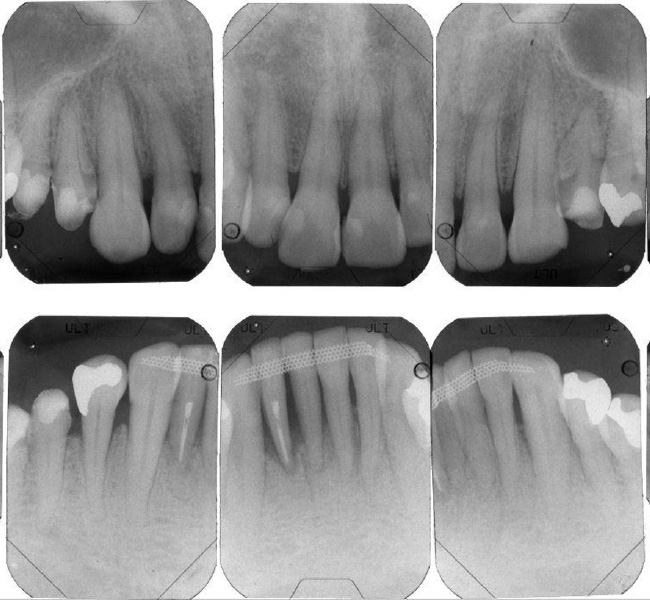

治療前

治療後

| 治療内容 | 全顎治療:歯周病治療、抜歯、根管治療、 咬合治療・矯正治療、フルメタルクラウン(保険) |